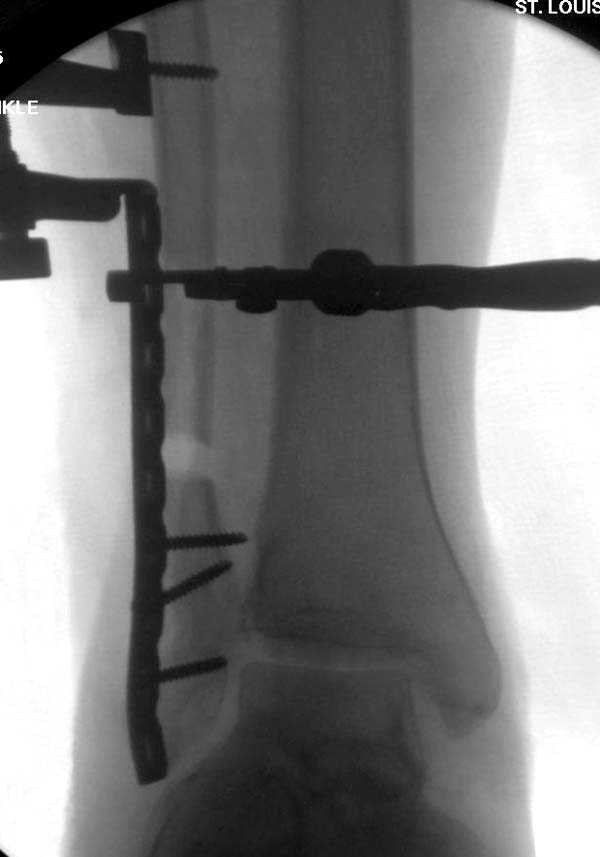

Проведена обычная стандартная процедура по исправлению неудовлетворительного состояния голеностопного сустава, где кроме удлинения малоберцовой с применением compression tension device за проксимальный конец пластины, проведено замещение трикортикальным графтом из крыла, освобождение синдесмоза и медиальной щели от

фибротических масс с фиксацией.